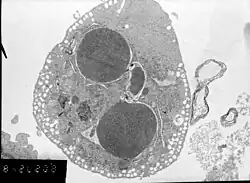

Label-free live cell imaging, time-lapse microscopy, flow fluorocytometry, and transmission electron microscopy can be used to compare apoptotic and necrotic cells. There are also various biochemical techniques for analysis of cell surface markers (phosphatidylserine exposure versus cell permeability by flow cytometry), cellular markers such as DNA fragmentation[80] (flow cytometry),[81] caspase activation, Bid cleavage, and cytochrome c release (Western blotting). Supernatant screening for caspases, HMGB1, and cytokeratin 18 release can identify primary from secondary necrotic cells. However, no distinct surface or biochemical markers of necrotic cell death have been identified yet, and only negative markers are available. These include absence of apoptotic markers (caspase activation, cytochrome c release, and oligonucleosomal DNA fragmentation) and differential kinetics of cell death markers (phosphatidylserine exposure and cell membrane permeabilization). A selection of techniques that can be used to distinguish apoptosis from necroptotic cells could be found in these references.[82][83][84][85]